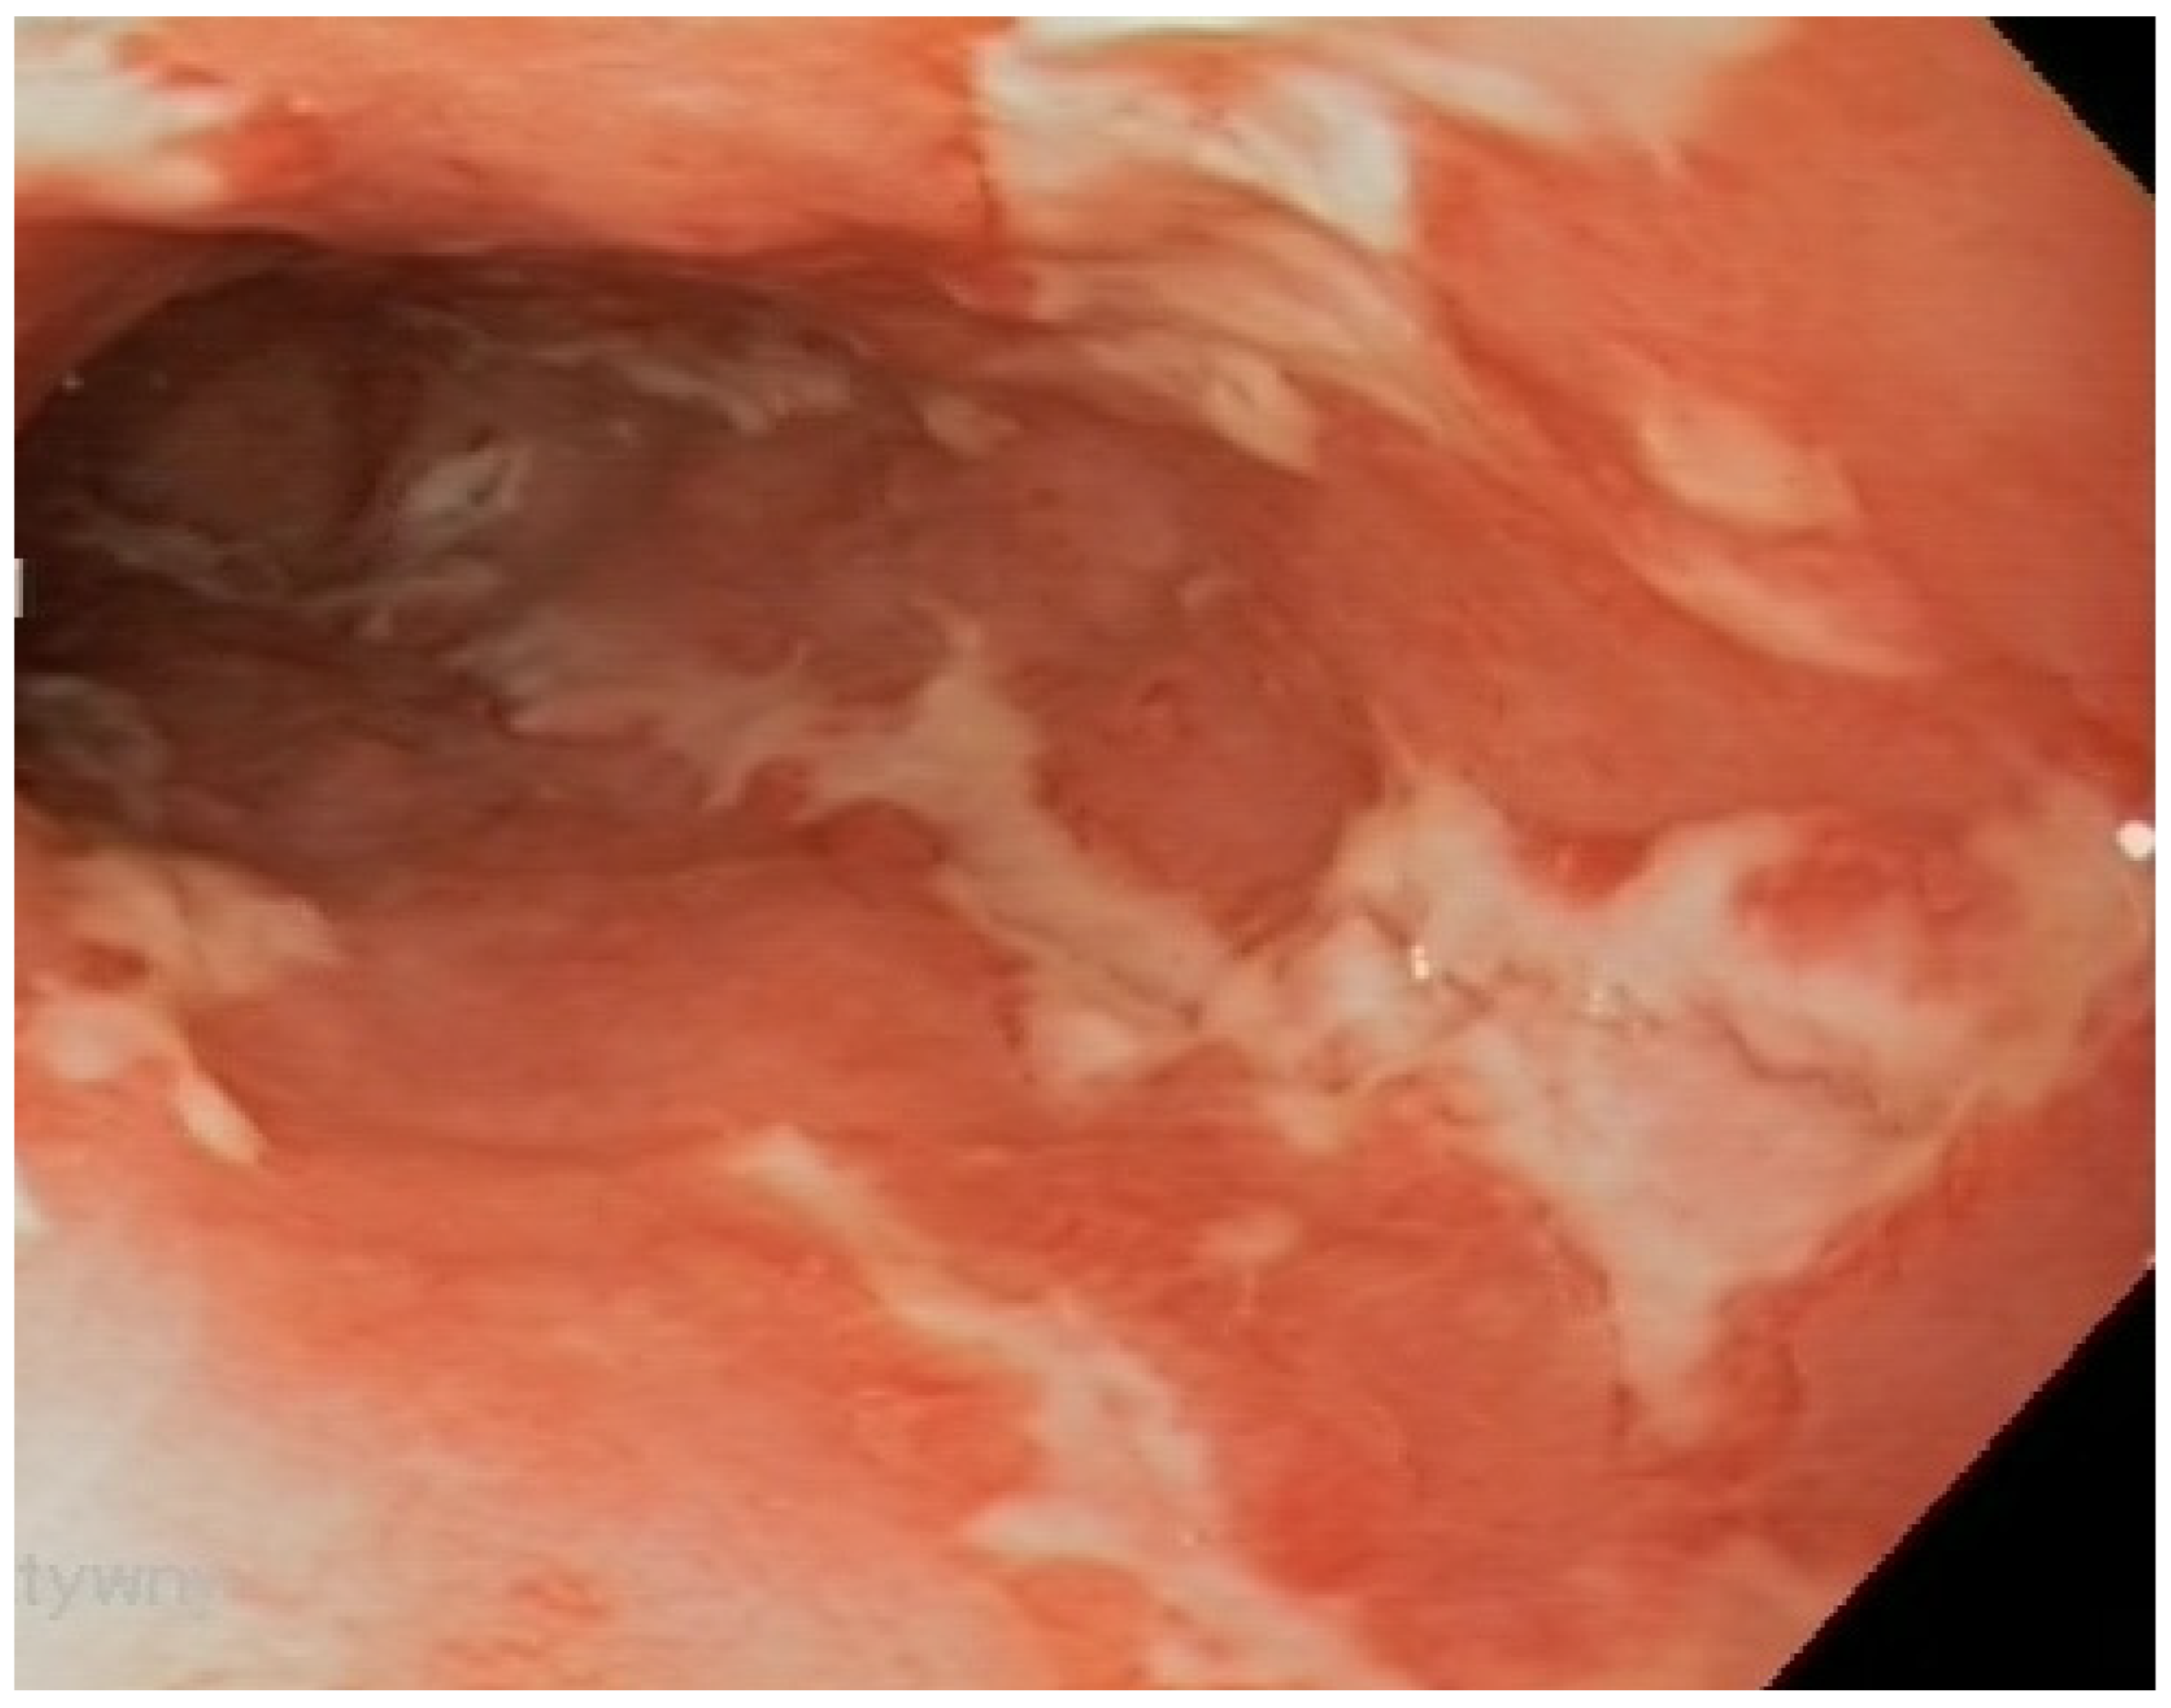

| Inflammation of upper digestive tract (esophagus, stomach, duodenum) | 16 [55.2] | |